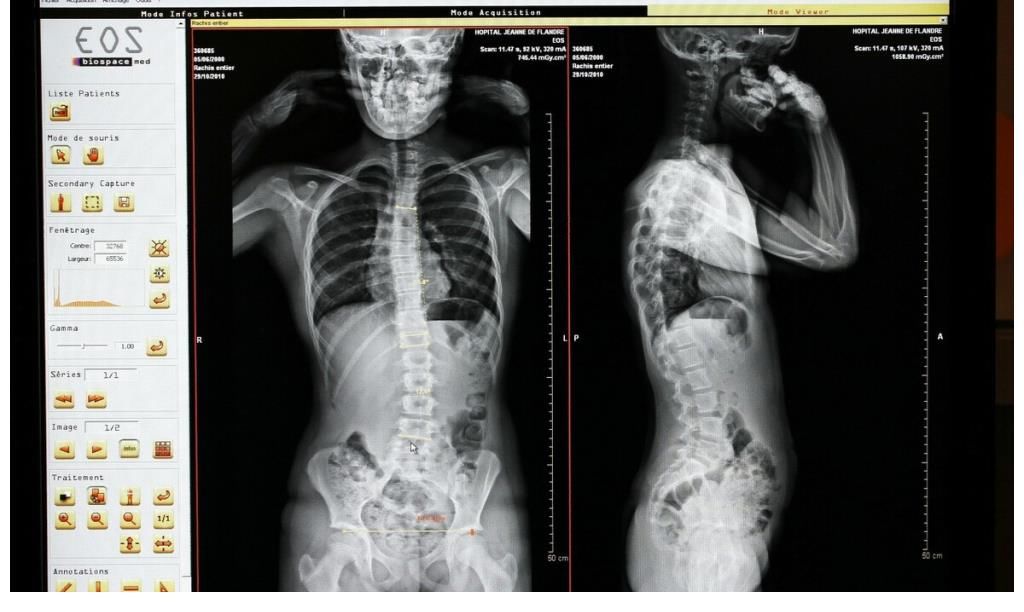

骨质疏松会给生活带来巨大的变化,变矮驼背会影响生活质量,腰酸背痛也会出现恶化的情况。如果发生了骨折,甚至可能带来长期残疾的风险。在我国大约有9000万的骨质疏松患者,这就表明我们应该多关注这种骨骼疾病。

骨质疏松的常见症状有3种,需要密切注意

很多人很难想到骨质疏松会与呼吸有联系。骨质疏松会导致腰椎发生侧弯,会压迫肺部,导致患者呼吸困难,胸闷气短。患者出现胸闷气短,严重情况下会出现窒息。患者一定要及时就医,不能延误。

3、容易骨折

骨折指的是脆性骨折,患者身体出现轻微的碰撞就会导致骨折。如果出现骨折就会严重的影响生活,患者应该避免摔跤和剧烈运动。